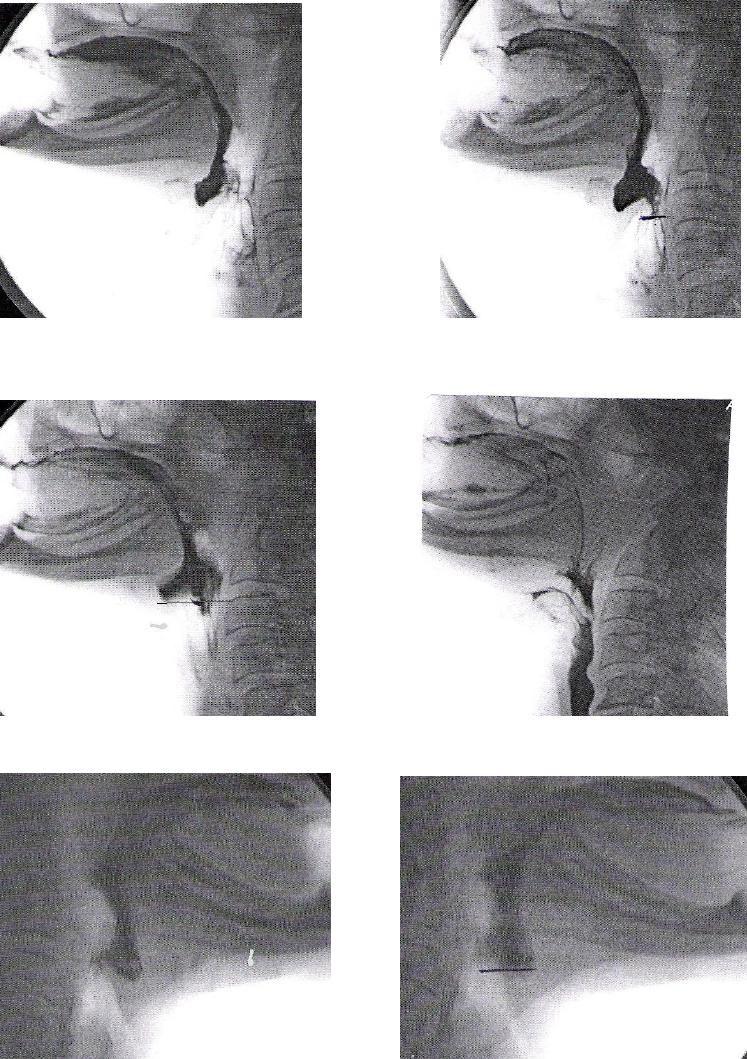

ANEXO E Imagens videofluoroscópicas da deglutição, registrando

escape prematuro e reação de deglutição atrasada, p e s

crioestimulação, com líquido e pastoso.........................................................